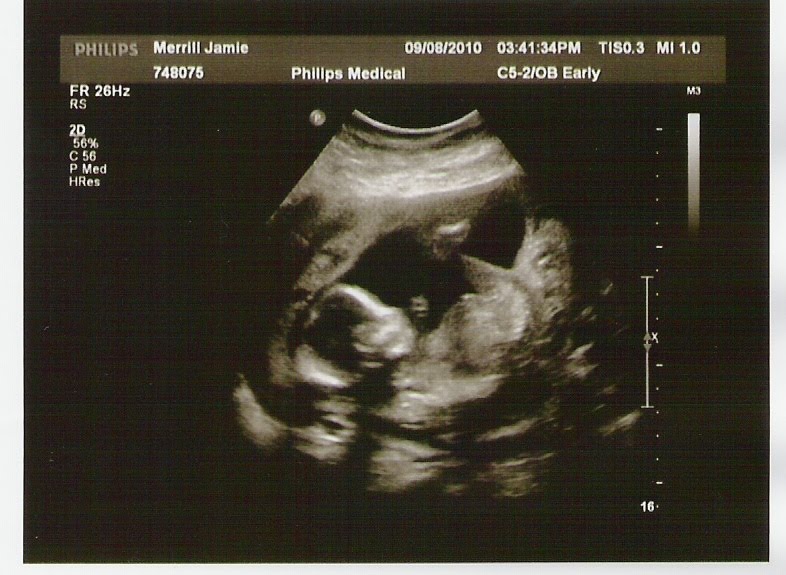

Today we had our appointment to see if our little baby was a boy or a girl. After the ultrasound tech looked for quite awhile (our baby’s a mover), we found out that it’s a girl! She is officially Elizabeth Katie Marie Roberts.

While the ultrasound tech was looking around, she had to take some measurements and make sure all the internal organs were in order. She took a TON of pictures (which is always great!).

This one is my favorite. You can really tell she has Mike's chin and nose, and you can see her little eyelashes.

She went to show the doctor her findings, but he said that our baby was still a little too small to make any judgments, so we have to go back on October 1st, which is fine by me since that just means we get to see our little girl again :)